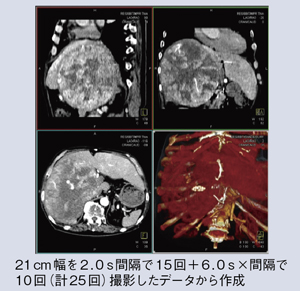

図2は,当院で作成した4D画像である。アキシャル像はもとより,コロナル,サジタルなど,さまざまな画像での観察も可能である。また,図3では非常に大きなHCCが認められるが,心臓から大動脈に造影剤が流入し,肝動脈を経て腫瘍が濃染していく様子が明瞭に描出され,あたかもDSAを3Dで見ているような画像となっている。将来的には,こうした画像の活用が肝動脈塞栓術のカテーテルのナビゲーションなどにも役立つのではないかと期待している。

![]() 図2 Adaptive 4D Spiralにより作成した4D画像 |